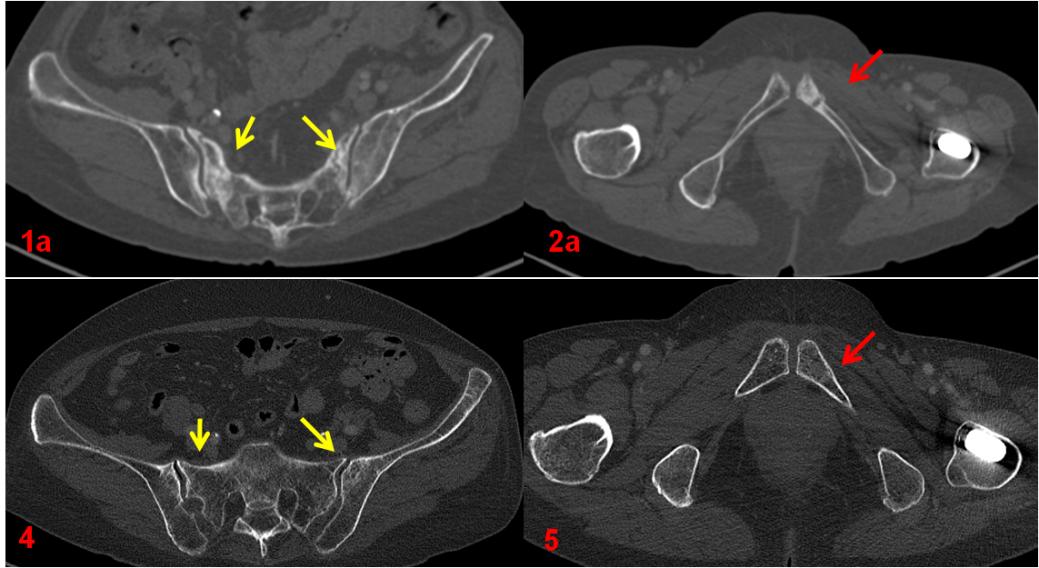

ECT全身骨顯像診斷為機能不全骨折,建議患者隨診復查?;颊哂?年后復查平掃CT及ECT全身骨顯像,綜合兩次影像學資料,考慮骨折修復愈合。

復查CT(圖4、5)對比前片(圖1a、2a)。前片所示骶骨密度不均勻增高(1a,黃箭),本次明顯恢復(4,黃箭),左側(cè)恥骨骨質(zhì)斷裂(2a,紅箭),本次基本消失(5,紅箭)。